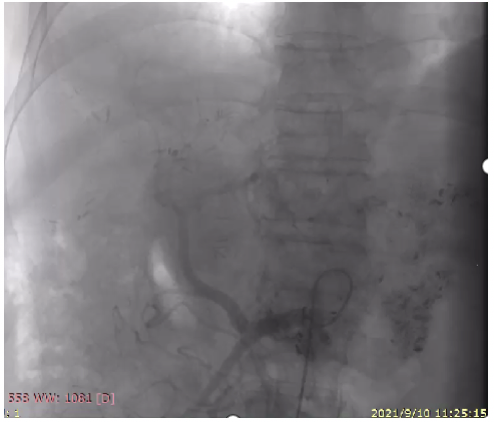

2021年9月10日行肝动脉灌注化疗(HAIC):超选至肝固有动脉后留置导管,灌注奥沙利铂150mg,亚叶酸钙700mg,氟尿嘧啶4750mg(46小时)(图4)。

图4. 2021年9月10日HAIC